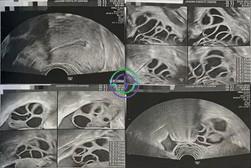

促排第 4 天 — LH 逐渐下降;卵泡发育正常

超声结果

右侧卵巢:卵泡大小 9, 9, 9, 8, 8, 7, 7, 6 mm → 共 8 个卵泡

左侧卵巢:卵泡大小 10, 9, 9, 9, 8, 8, 8, 8, 6, 6, 6, 6 mm → 共 12 个卵泡

激素结果

LH:8.8 mIU/mL